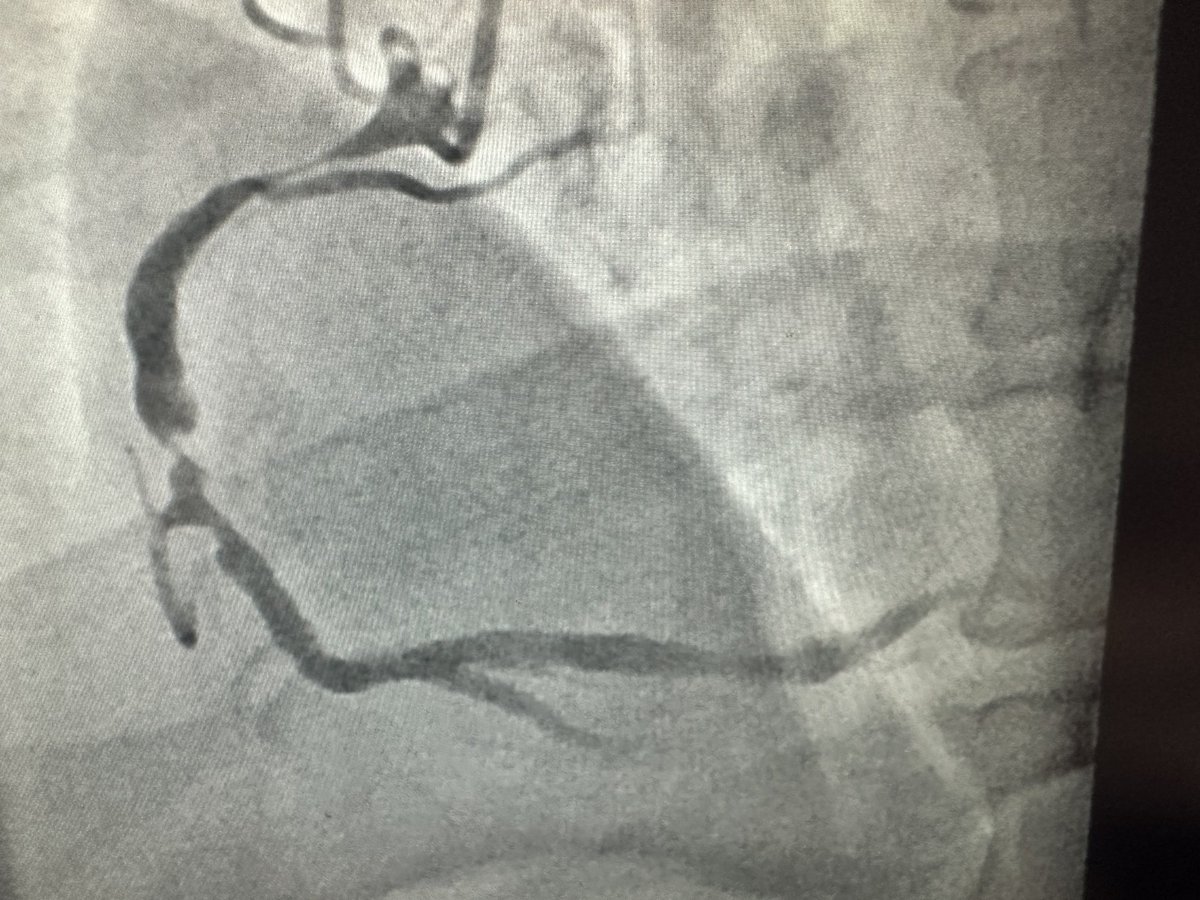

Read 🔟 key points from a state-of-the-art review on multimodality imaging in the diagnostic work-up of patients with cardiac masses. 🔗 bit.ly/3YP5TTY